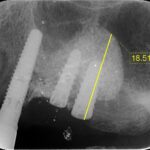

本日は、ラテラルスリット法によるサイナスリフトを行いました。